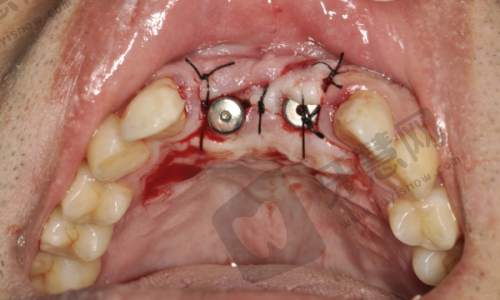

保定北京儿童医院种植牙方案价格实惠,擅长德国费亚丹Frialit、诺贝尔平替、德国sky、韩国仕诺康、韩国登腾Super LineⅡ、locator种植技术,还提供缺骨种植牙服务。推荐就诊黄滕医生、陈思语医生、崔芷茹医生。

1、黄腾:男士,拥有超过18年的丰富临床经验,现任保定北京儿童医院牙科种植牙主治医师。擅长于儿童种植牙手术、上颚种植、颧骨穿孔种植、以及杆卡式种植修复。

保定北京儿童医院种植牙价格:低5980元一颗起、半口种植牙34452元起、全口种植牙57846元起

缺骨种植牙5980元一颗起;

穿颧骨种植牙6579元一颗起;

植骨后种植牙6080元一颗起;

locator种植覆盖义齿6412元一颗起;